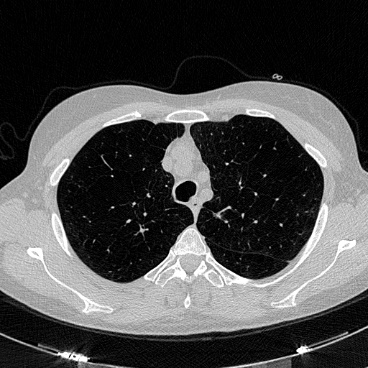

相关图片展示: